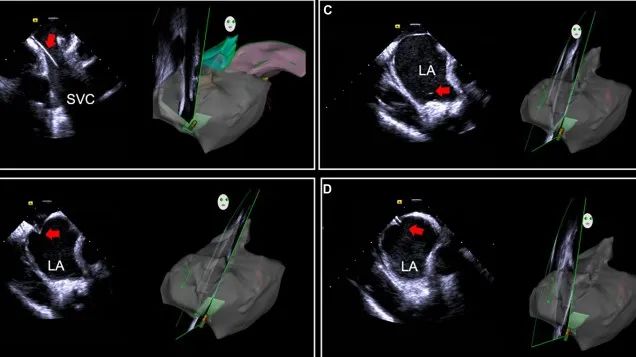

一種與心導(dǎo)管檢查相結(jié)合的超聲心動(dòng)圖診斷新興技術(shù),通過將超聲探頭置于心腔內(nèi)部,發(fā)射并接收超聲信號,來精確獲取心臟解剖結(jié)構(gòu)、心臟血流動(dòng)力學(xué)等信息的實(shí)時(shí)成像。與其他影像技術(shù)相比,ICE技術(shù)具有操作簡單、無輻射、安全性高、手術(shù)效率高、實(shí)用等優(yōu)勢,ICE在很大程度上有望取代經(jīng)食道超聲心動(dòng)圖(TEE),成為電生理和結(jié)構(gòu)性心臟病領(lǐng)域的理想成像方式。

目前ICE技術(shù)已被應(yīng)用于左心耳封堵、房顫射頻消融、二尖瓣成形、房間隔缺損封堵等多種心臟介入手術(shù),應(yīng)用場景主要圍繞心臟電生理、結(jié)構(gòu)性心臟病等領(lǐng)域,目前以電生理應(yīng)用為主。數(shù)據(jù)顯示,我國結(jié)構(gòu)性心臟病介入器械市場規(guī)模已從2017年的4億元增長至2021年的20億元,年復(fù)合增長率達(dá)48.3%;預(yù)計(jì)到2025年,該市場規(guī)模將達(dá)到104億元,可以預(yù)見ICE市場規(guī)模也將同步高速增長,未來市場發(fā)展空間廣闊。

心腔內(nèi)超聲(ICE)技術(shù)壁壘極高,國內(nèi)主要廠商核心部件仍舊為進(jìn)口,集成了超聲和圖像處理最前端技術(shù),包括超聲探頭、線纜、軟件成像算法等,是當(dāng)前內(nèi)窺超聲方向最具挑戰(zhàn)的領(lǐng)域。ICE的應(yīng)用經(jīng)歷了2D平面成像、3D三維立體成像、以及4D的實(shí)時(shí)三維立體成像階段。